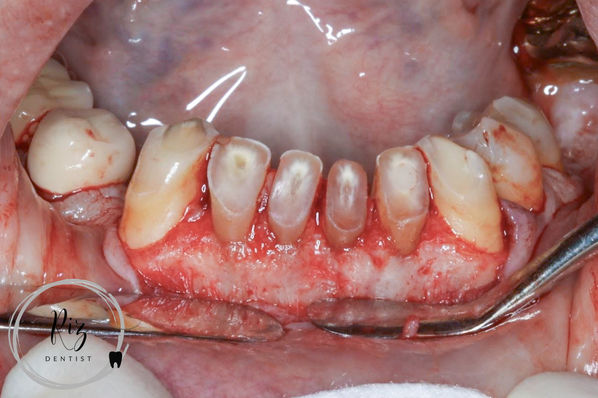

Crown Lengthening Surgery:

To achieve sufficient crown height, we performed surgical crown lengthening on the lower anterior teeth using a surgical stent. This procedure was carried out by a periodontal colleague.

This very pleasant patient presented to us with very old upper crown and bridgework that had started to recede, resulting in an unsightly appearance. Additionally, the patient experienced severe attrition on the lower anterior teeth, with a few teeth worn down almost to the gingival level. Seeking a second opinion after being advised by their general dental practitioner (GDP) to extract the affected teeth, the patient approached us for a comprehensive solution.